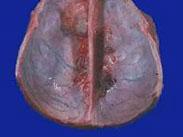

顱內出現兩個以上相互不連接的腦膜瘤稱為多發性腦膜瘤,至今文獻中報道約400例。1822年,Wishart首先報道1例21歲男性多發腦膜瘤,該病人同時有顱骨增厚和雙側神經瘤。按現代的觀點,這例應屬Ⅱ型神經纖維瘤病(Reck linghausen’s disease)文獻報道中約有一半患者是首次診斷即發現多個腦膜瘤,而另有約一半患者是首次診斷發現后的一段時間內又在其他部位發現一個或多個腦膜瘤。多發腦膜瘤多見于大腦凸面,分散在一個大腦膜瘤周圍,也可發生于顱底。有時可見多個腦膜瘤同時出現在腦室內與腦室外,或同時發生于幕上和幕下。另外,臨床上還常見顱內腦膜瘤與聽神經瘤或椎管內脊膜瘤同時存在的情況。任何類型的腦膜瘤均可在多發性腦膜瘤中發現。